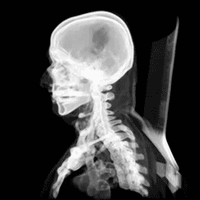

Injuries to the brain can be life-threatening. Normally the skull protects the brain from damage through its high resistance to deformation; the skull is one of the least deformable structures found in nature, needing the force of about 1 ton to reduce its diameter by 1 cm.[20] In some cases of head injury, however, there can be raised intracranial pressure through mechanisms such as a subdural haematoma. In these cases, the raised intracranial pressure can cause herniation of the brain out of the foramen magnum ("coning") because there is no space for the brain to expand; this can result in significant brain damage or death unless an urgent operation is performed to relieve the pressure. This is why patients with concussion must be watched extremely carefully. Repeated concussions can activate the structure of skull bones as the brain's protective covering.[21]

Dating back to Neolithic times, a skull operation called trepanning was sometimes performed. This involved drilling a burr hole in the cranium. Examination of skulls from this period reveals that the patients sometimes survived for many years afterward. It seems likely that trepanning was also performed purely for ritualistic or religious reasons. Nowadays this procedure is still used but is normally called a craniectomy.

In March 2013, for the first time in the U.S., researchers replaced a large percentage of a patient's skull with a precision, 3D-printed polymer implant.[22] About 9 months later, the first complete cranium replacement with a 3D-printed plastic insert was performed on a Dutch woman. She had been suffering from hyperostosis, which increased the thickness of her skull and compressed her brain.[23]

A study conducted in 2018 by the researchers of Harvard Medical School in Boston, funded by National Institutes of Health (NIH), suggested that instead of travelling via blood, there are "tiny channels" in the skull through which the immune cells combined with the bone marrow reach the areas of inflammation after an injury to the brain tissues.[24]